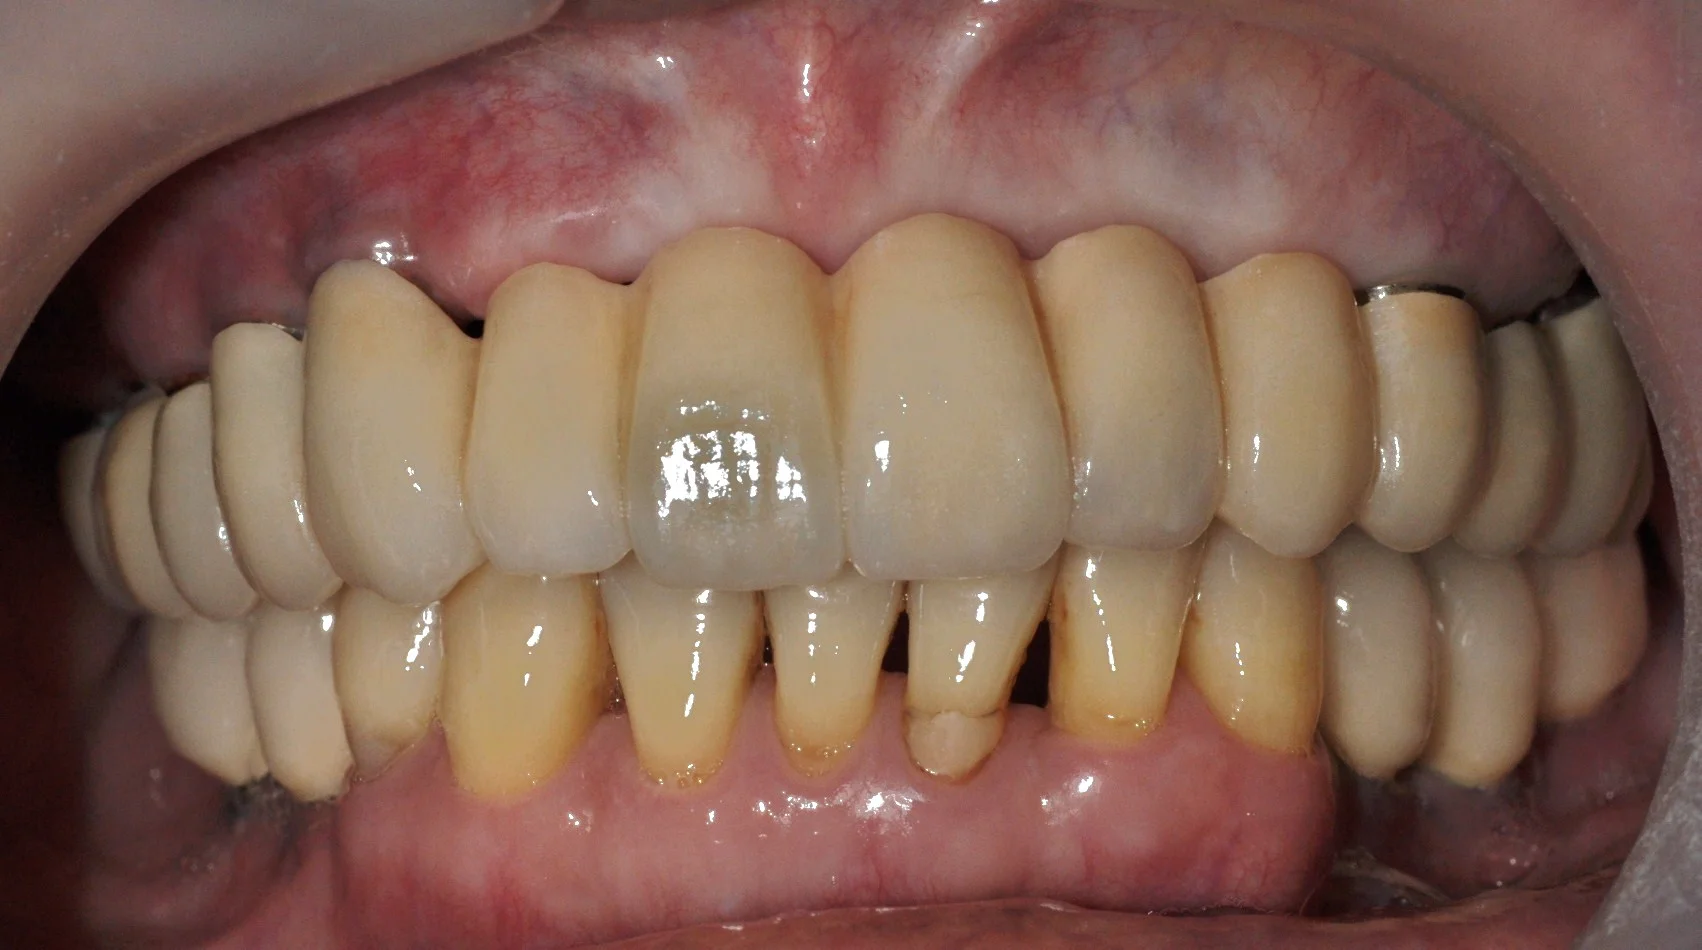

DSC_0285.JPG

AFTER

Dental X-ray showing several dental implants, crowns, and bridges in the upper and lower jaw.

MULTIPLE TEETH REPLACEMENT

(WITH DENTAL IMPLANTS)